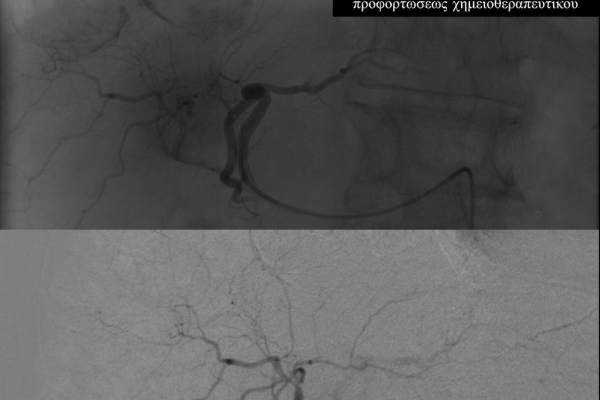

Ο χημειοεμβολισμός είναι μέθοδος τοπικής χημειοθεραπείας για πρωτοπαθή και δευτεροπαθή νεοπλάσματα του ήπατος. Σκοπός του είναι η τοπική έγχυση χημειοθεραπευτικού σε κλάδους της ηπατικής αρτηρίας, ώστε να επιτευχθούν υψηλές συγκεντρώσεις τοπικά στην ηπατική εξεργασία χωρίς να προκαλούνται οι συστηματικές επιπλοκές τοξικότητας του χημειοθεραπευτικού. Επιπλέον προκαλείται τοπική ισχαιμία στην περιοχή του όγκου από τα εμβολικά υλικά-μικροσφαιρίδια εμβολισμού.